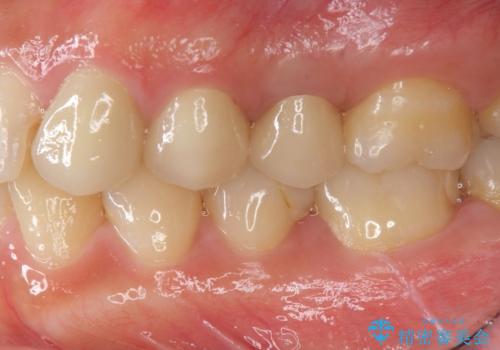

- 47.3万円(仮歯×3・ファイバーコア・ジルコニアクラウン×3・部分小矯正)費用は治療当時の料金となります

小矯正を行い深い虫歯を改善した後は、小手術を行うことで歯ぐき・周囲歯槽骨の状態を整えることでより安定した歯周環境を得ることができます。